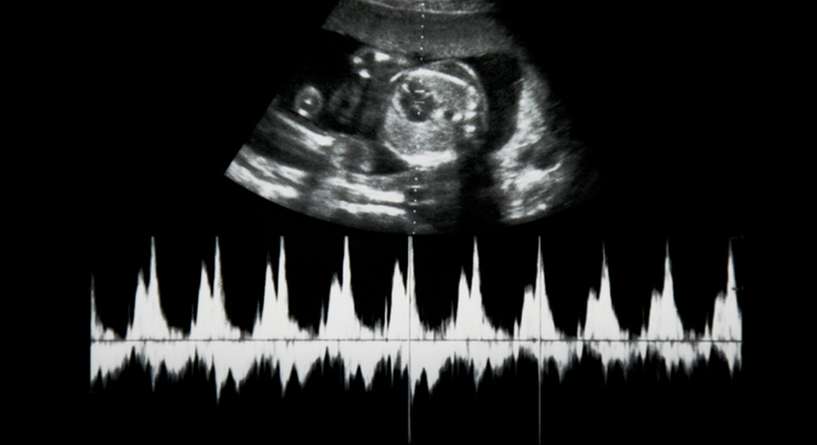

إذا للتأكد من سير أمور الحمل بالشكل الطبيعي، قد يقوم الطبيب بإجراء تخطيط قلب الجنين إذ يعمل الجهاز المتوفر في المستشفيات على تسجيل نبضات قلب الطفل خلال فترة عشرين او ثلاثين دقيقة. ويظهر نبض الجنين السليم عادة على شكل خط متعرج.